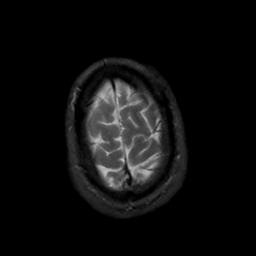

MR Study #5, March 10, 1991 -- Slice #46

[Home][Help][Clinical][Tour 1][Tour 2] Slice 46